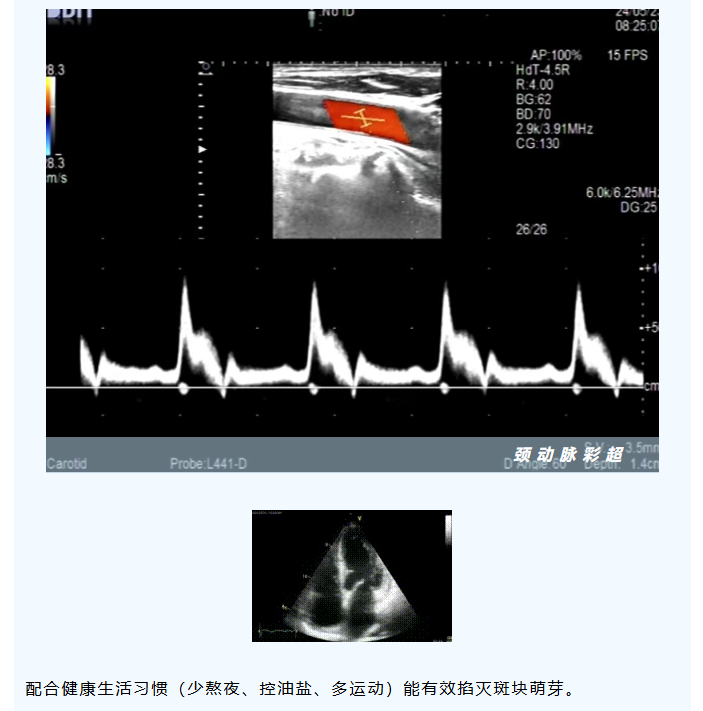

血管的“一生历险记”与“救命指南”—— 在世界心脏病日,读懂您“心”的呼唤